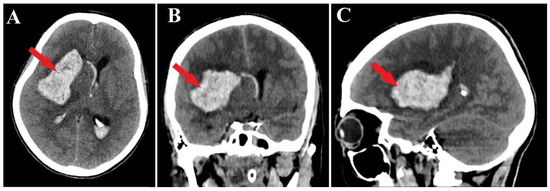

Figure 1.

Preoperative CT scan. Axial section (A) highlights the intraparenchymal hematoma (red arrow); moreover, frontal (B) and sagittal (C) sections depict the massive hematoma with panventricular implication too (red arrows).

A 44-year-old patient was admitted to our clinic for sudden left hemiparesis MRC 1/5 occurring in the apparent health status 48 h prior to admission, followed by the deterioration of consciousness that become gradually worse, with the patient becoming comatose. She was admitted to our clinic with GCS = 7 points (eye response—2 points, verbal response—2 points, motor response—3 points), orotracheally intubated, and mechanically ventilated. Neurological examination on admission revealed a left hemiparesis, predominantly in the brachial region and comatose state. A brain non-contrast CT scan revealed a voluminous right fronto-temporal intraparenchymal hematoma with panventricular infiltration, significant mass effect on the right lateral ventricle, and 1.5 cm displacement of the midline. Otherwise, normal cerebroventricular CT appearance was seen (Figure 1). Angiography was performed through the selective injection of the internal carotid artery bilaterally, right external carotid artery, and left vertebral artery. Right temporal arteriovenous malformation with arterial afferents from the right anterior choroidal artery and right-sided middle cerebral artery was observed, Spetzler Martin grade III (Figure 2). A nidus of approximately 2/1 cm in size with several intranidal aneurysms was also observed (Figure 3). A single vein was draining into the right cavernous sinus, through an intermediate venous source.